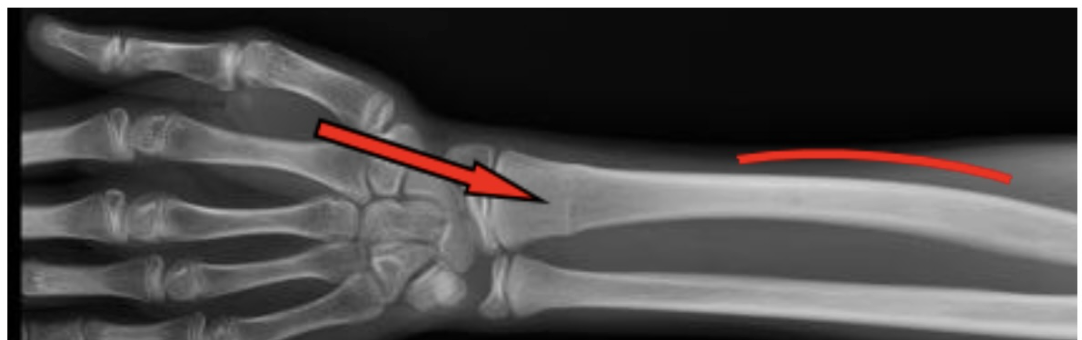

polsfractuur:

Wanneer conservatief?

Wanneer operatief?

Stabiel, niet-verplaatst → gips.

Instabiel

Intra-articulair

Slechte repositie

belangrijkste complicaties polsfractuur

Compartimentsyndroom

Carpaal tunnelsyndroom

CRPS

Zenuwschade